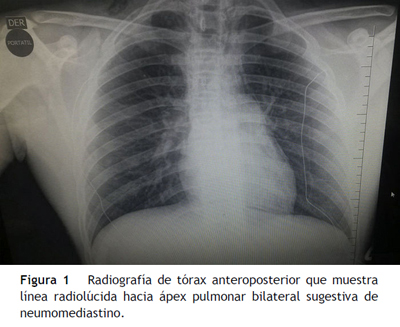

En la radiografía de tórax se evidenció imagen radiolúcida en ápex pulmonar bilateral sugestiva de neumomediastino (fig. 1).

En el enfoque inicial, la radiografía del tórax en proyección frontal y lateral (con una sensibilidad de 89,1%) y la radiografía del cuello en proyección lateral (con una sensibilidad de 95,2%) son las herramientas más importantes para su detección, y se pueden encontrar líneas o burbujas de aire rodeando las estructuras mediastinales, enfisema subcutáneo y colecciones de aire prevertebral14, como las observadas en este caso.